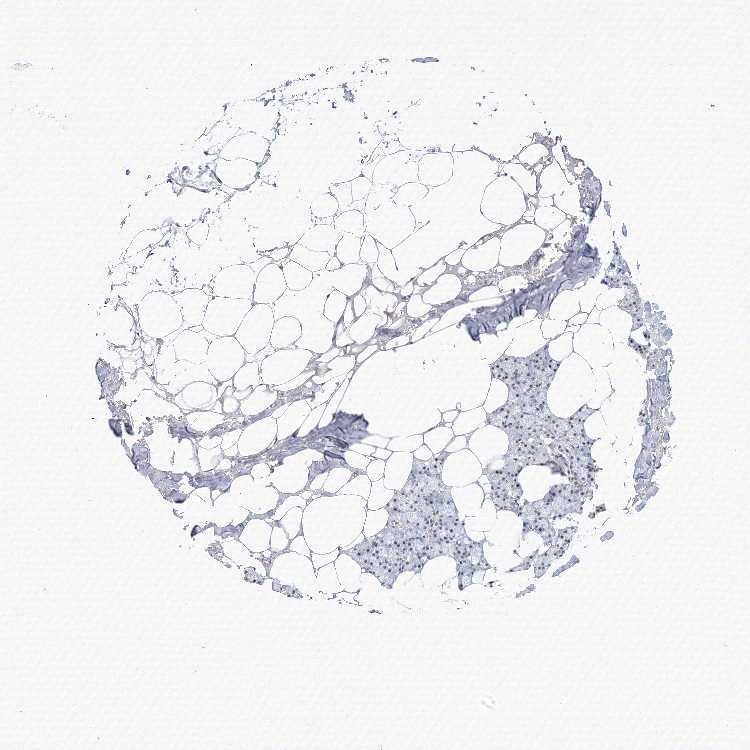

SALIVARY GLAND - Antibody stainingi

Antibody staining in the annotated cell types in the current human tissue is reported as not detected, low, medium, or high, based on conventional immunohistochemistry profiling in selected tissues. This score is based on the combination of the staining intensity and fraction of stained cells.

Each image is clickable and will lead to virtual microscopy that enables deeper exploration of all samples and also displays staining intensity scores, fraction scores and subcellular localization as well as patient and tissue information for each sample.

Antibody HPA034829Antibody HPA034830

Glandular cells LowLow